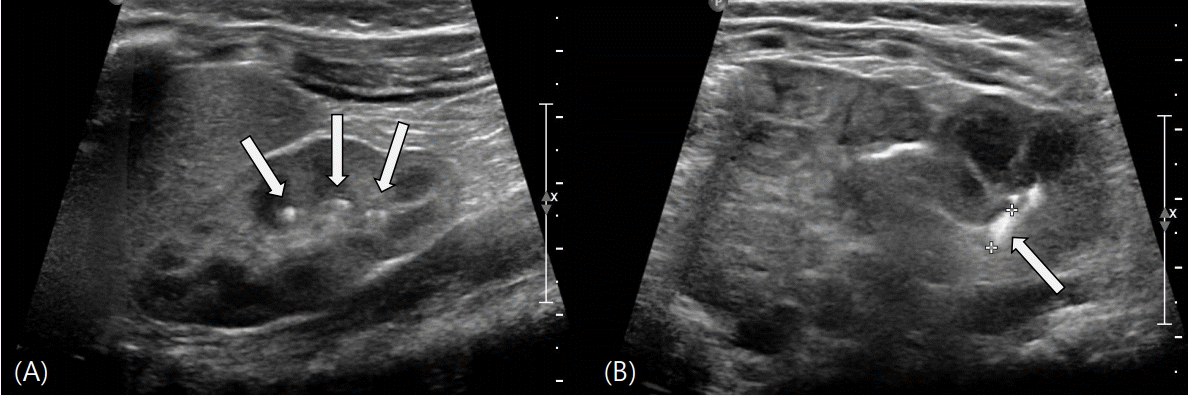

In a renal ultrasonography conducted because of persistent hypercalciuria, multiple small calyceal stones in both kidneys and a 0.6-cm stone in the left renal pelvis were newly observed, and hydronephrosis was absent (Fig. 3). Except for the dose of thiazide, the doses of the other drugs (calcium carbonate, magnesium, and calcitriol) were decreased. We carefully monitored the neonate for convulsions, and the serum calcium, phosphorus, magnesium, and urinary calcium excretion rate were checked regularly. On day 7 after readmission, calcitriol dose was decreased from 1.5 to 0.125 μg/day and the calcium dose was decreased to 20 mg/kg/day. In a blood test conducted 2 days later, the serum calcium level was found to be low (6.6 mg/dL). Consequently, the calcium carbonate dose was increased and maintained at 40 mg/kg. Due to hypercalciuria (spot urine calcium/creatinine ratio, 1.03), the thiazide dose was increased from 0.5 to 1.5 mg/kg, and the patient was discharged after we decided to control the doses in an outpatient setting.